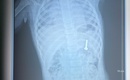

Y tế - 07/08/2024 06:50Thông tin từ Bệnh viện Quân y 175, TPHCM, chiều 6/8, trực thăng EC-225 mang số hiệu 8619 của Binh đoàn 18 đã hạ cánh xuống sân đỗ nóc tòa nhà Viện Chấn thương chỉnh hình (Bệnh viện Quân y 175) đưa ba nạn nhân bị tai nạn lao động, chấn thương nặng từ huyện đảo Trường Sa (tỉnh Khánh Hòa) về đất liền an toàn.

Y tế huyện đảo Bạch Long Vĩ cứu sống bệnh nhân viêm ruột thừa ngày thứ 3

Y tế - 20/03/2023 18:27SKĐS - Khi thấy cơn đau bụng ngày một tăng, kèm sốt cao, bệnh nhân tự mua thuốc về uống nhưng không đỡ. Bệnh nhân được đưa vào Trung tâm y tế quân dân y Bạch Long Vĩ cấp cứu.

Y tế Bạch Long Vĩ, Hải Phòng: Vượt khó, cứu người bệnh nơi trùng khơi

Y tế - 15/03/2023 19:41SKĐS - Nằm xa đất liền, hoạt động trong điều kiện thời tiết khắc nghiệt, công tác chăm sóc sức khỏe và khám chữa bệnh nơi đảo xa Bạch Long Vĩ đã từng bước vượt khó, cấp cứu thành công nhiều ca gặp nạn ngoài khơi

Kỳ tích những ca phẫu thuật cứu người trên quần đảo Trường Sa

Sự hi sinh thầm lặng - 25/02/2022 07:30SKĐS - Với khoảng cách xa đất liền hàng ngàn cây số, những bệnh xá ở quần đảo Trường Sa (tỉnh Khánh Hòa) đóng vai trò quan trọng trong công tác chăm sóc sức khỏe quân, dân hoạt động trên vùng biển Việt Nam.